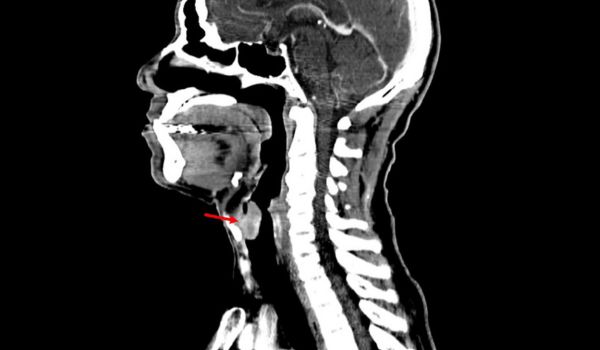

Радіологічні особливості при виборі хірургічної тактики лікування пухлин гортані